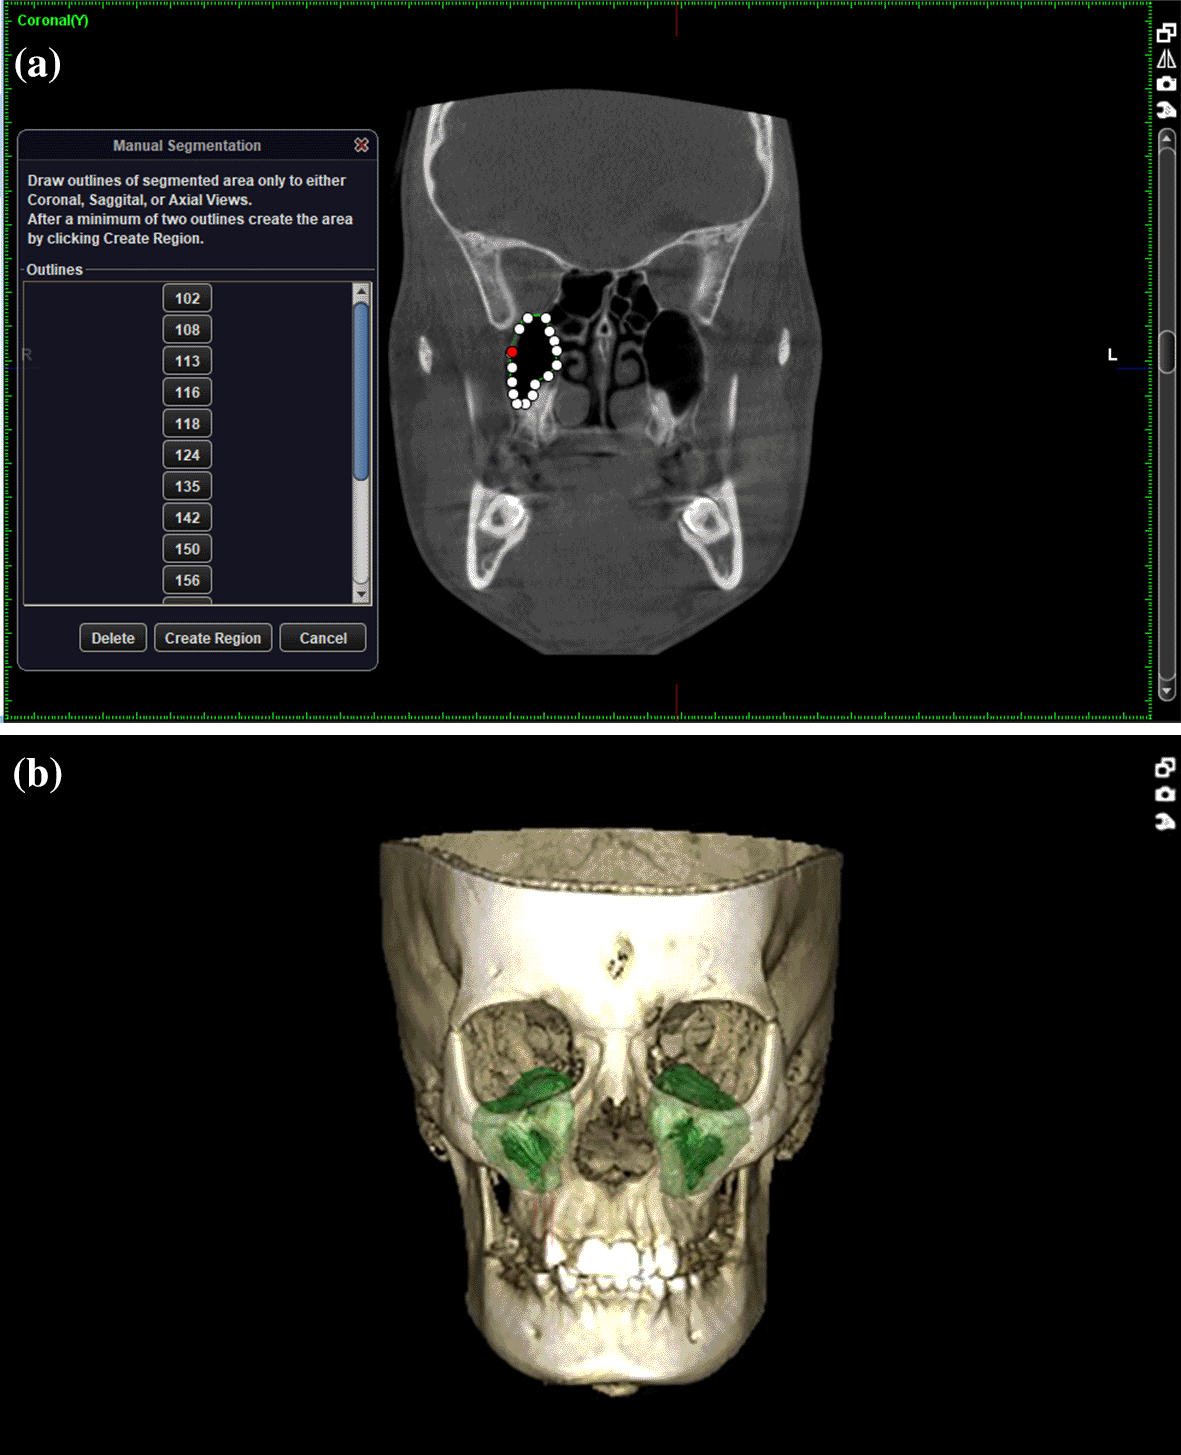

A total of 66 full FOV CBCT scans of patients satisfying inclusion and exclusion criteria were collected from the department archives. The CBCT images were previously obtained with patients written consent for diagnostic purpose using Planmeca ProMax Machine (230-240 V, 50 Hz, 16 A) manufactured by Planmeca OY (Helsinki Finland). The images were in DICOM file format and were analysed using Planmeca Romexis Viewer (Version 5.1.0.4). All the records were analysed by a single observer. Three locations were chosen to measure sinus height and basal bone height: PM1-PM2(between premolars), PM2-M1(between 2nd premolar and 1st molar), M1-M2(between molars).

Following measurements were recorded bilaterally and mean value was obtained; Figures: 1-3

5. Volume of the maxillary sinusz